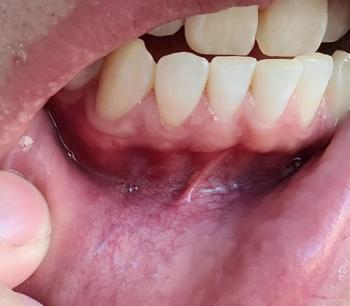

The image shows generalized heavy plaque and tartar (calculus) accumulation, especially on the lower anterior and posterior teeth, with visible gum inflammation, discoloration, and possible active decay. Tooth surfaces appear rough, yellow-brown, and uneven—signs of long-standing poor oral hygiene and bacterial overload.

This is not an early-stage case. The disease has likely been progressing for months or years.